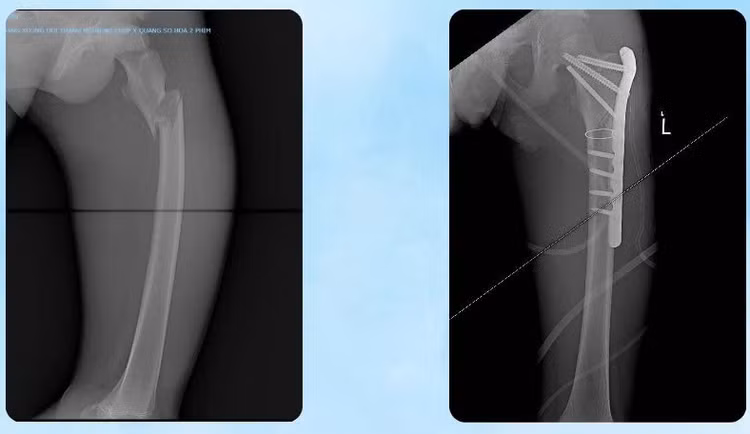

Khoa Ngoại Chấn thương – Bỏng: Thực hiện phẫu thuật kết hợp xương đùi dưới C-arm bằng đường mổ nhỏ, nắn chỉnh tốt giải phẫu ổ gãy, kết hợp xương bằng nẹp vít khóa.

Hình ảnh kết hợp xương đùi gãy - Ảnh BVCC